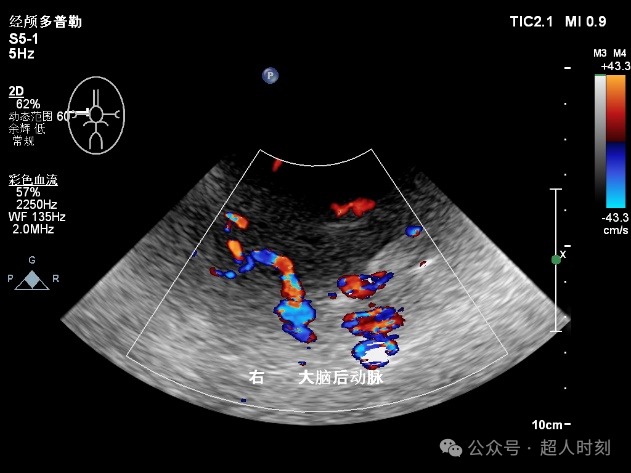

图5c 右大脑后动脉狭窄

图5d 右大脑后动脉血流增快频谱(VP:140cm/s)